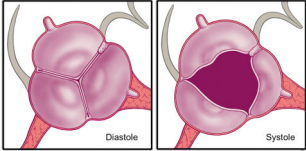

正常主动脉瓣由3个半月瓣组成,称三叶式主动脉瓣(tricuspid aortic valve, TAV),根据瓣膜位置及冠状动脉开口可将其分为左、右和无冠状动脉瓣。而BAV因主动脉瓣发育异常导致相邻两个半月瓣形成融合瓣,部分融合瓣上可见融合嵴,使瓣叶不对称。

最新国际共识认为仅基于外科角度的Sievers分型仍有局限性,因此新的分型为:融合型、双窦型和部分融合型。其中融合型最常见,占90%~95%,相当于TypeⅠ型。双窦型BAV并不常见,占5%~7%,由大小、形状大致相同的两个瓣叶构成,分前侧对侧表型和前后表型(图b)。部分融合型的流行率尚不清楚,表现为典型的三叶瓣膜,但在连合底部可见<50%的瓣尖融合。至于Sievers分型中的Type Ⅱ型,共识认为称单叶瓣较为合适。

双窦型